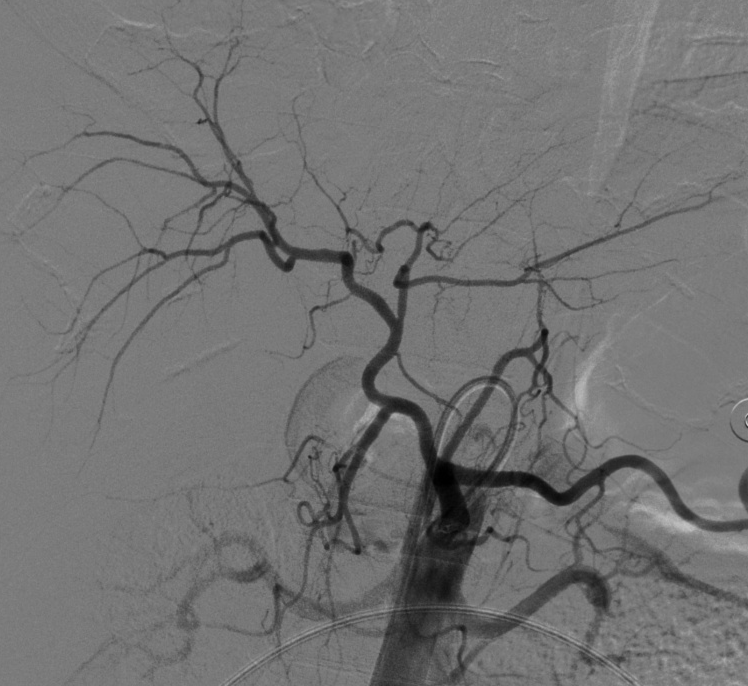

入院后,为患者给予补液,在局部麻醉下行DSA引导下经导管肝肿瘤动脉栓塞术。

肝癌破裂大出血并失血性休克患者往往病情急、危、重,如果治疗不及时可能短期内死亡。未开展介入治疗的医院对此类患者只能给予输血,补液,急诊手术,在插管全麻下行开腹手术治疗。但开腹手术往往切口长、手术时间长、手术创伤大,麻醉副作用大。可能术后出现肝功能衰竭,再出血,腹腔感染,切口疼痛,切口感染等并发症。介入手术则往往较少出现这些并发症。介入手术只需要在腹股沟穿刺一个2mm的小孔,置入导管到肝动脉,注入栓塞剂栓塞肝肿瘤的动脉,手术创伤小,止血可靠,除肝区疼痛及发热外,较少出现其它并发症,病人舒适度明显提高,而且能早期进食及下地活动,恢复快,能缩短住院时间,具有疗效好且微创的优点。